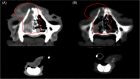

Methods: Retrospective study of cats treated with SBRT between 2010 and 2020 at Colorado State University. Diagnosis of nasal lymphoma was obtained via cytology or histopathology. Signalment, radiation protocol, concurrent treatments, adverse effects, and survival were recorded.

Results: Progression free survival was 225 days (95% CI 98-514) and median survival time (MST) was 365 days (95% CI 123-531). No significant difference in survival was identified between cats that received 1 versus greater than 1 fraction (MST 427 vs. 123 days, P = 0.88). Negative prognostic factors included cribriform lysis (MST 121 vs. 876 days, P = 0.0009) and intracalvarial involvement (MST 100 vs. 438 days, P = 0.0007). Disease progression was noted in 38% (12/32), locally in 22% (7/32), and systemically in 16% (5/32). No cats developed acute adverse effects. Ten cats developed late adverse effects: keratitis/keratitis sicca (n = 2), alopecia (n = 4), and leukotrichia (n = 4). Twenty-four cats (75%) had signs consistent with chronic rhinitis.